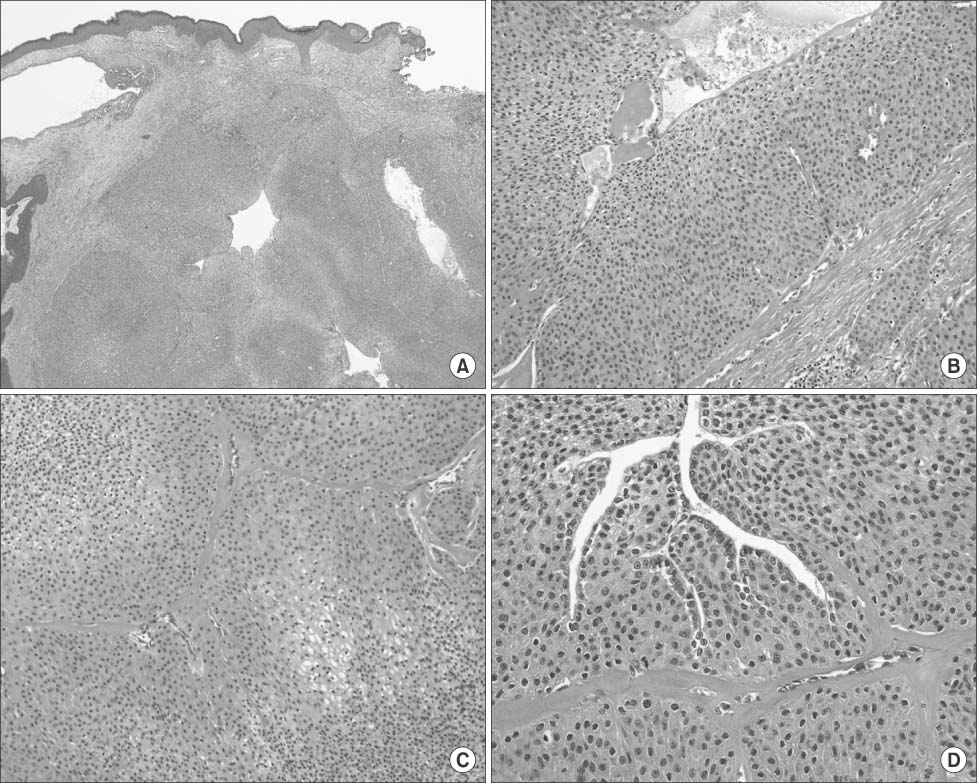

Fig. 2). Excisional operation was done, and histopathologic examination showed a well-demarcated lobulated dermal nodule, with solid and cystic areas. The lesion was centrally located in the dermis, with no connection to the overlying epidermis. Both solid and cystic areas consisted of polygonal cells, with abundant eosinophilic to pale cytoplasm. Occasional ductal differentiation lined by cuboidal epithelium was observed. No nuclear atypia, necrosis or abnormal mitosis was found (

Fig. 3). The histological findings were consistent with the diagnosis of nodular hidradenoma. During 3 years of the follow up period, the tumor didn't recur.

Fig. 3(A) Microphotograph shows solid and partially cystic mass in dermis. No connection was found between the lesion and epidermis (H&E stain, ×100). (B, C) Microphotograph shows polygonal cells with eosinophilic to clear cytoplasm in both solid and cystic areas (H&E stain, ×200). (D) Microphotograph shows ductal differentiation. Hyalinization of fibrous stroma is identified (H&E stain, ×400).